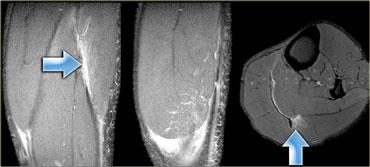

Bên trái là cùng một bệnh nhân.

Cũng có tổn thương mức độ trung bình ở đầu trong.

Lưu ý các ổ tích tụ dịch xung quanh đầu cơ.

Dịch càng nhiều, mức độ tổn thương càng cao.

Bên trái là cơ thẳng đùi bị tổn thương.

Các hình ảnh cho thấy tổn thương mức độ vừa, với sự biến dạng cấu trúc và một ổ tụ dịch (mũi tên).

Lưu ý phù nề tại chỗ nối cơ-gân dạng hai lông chim.